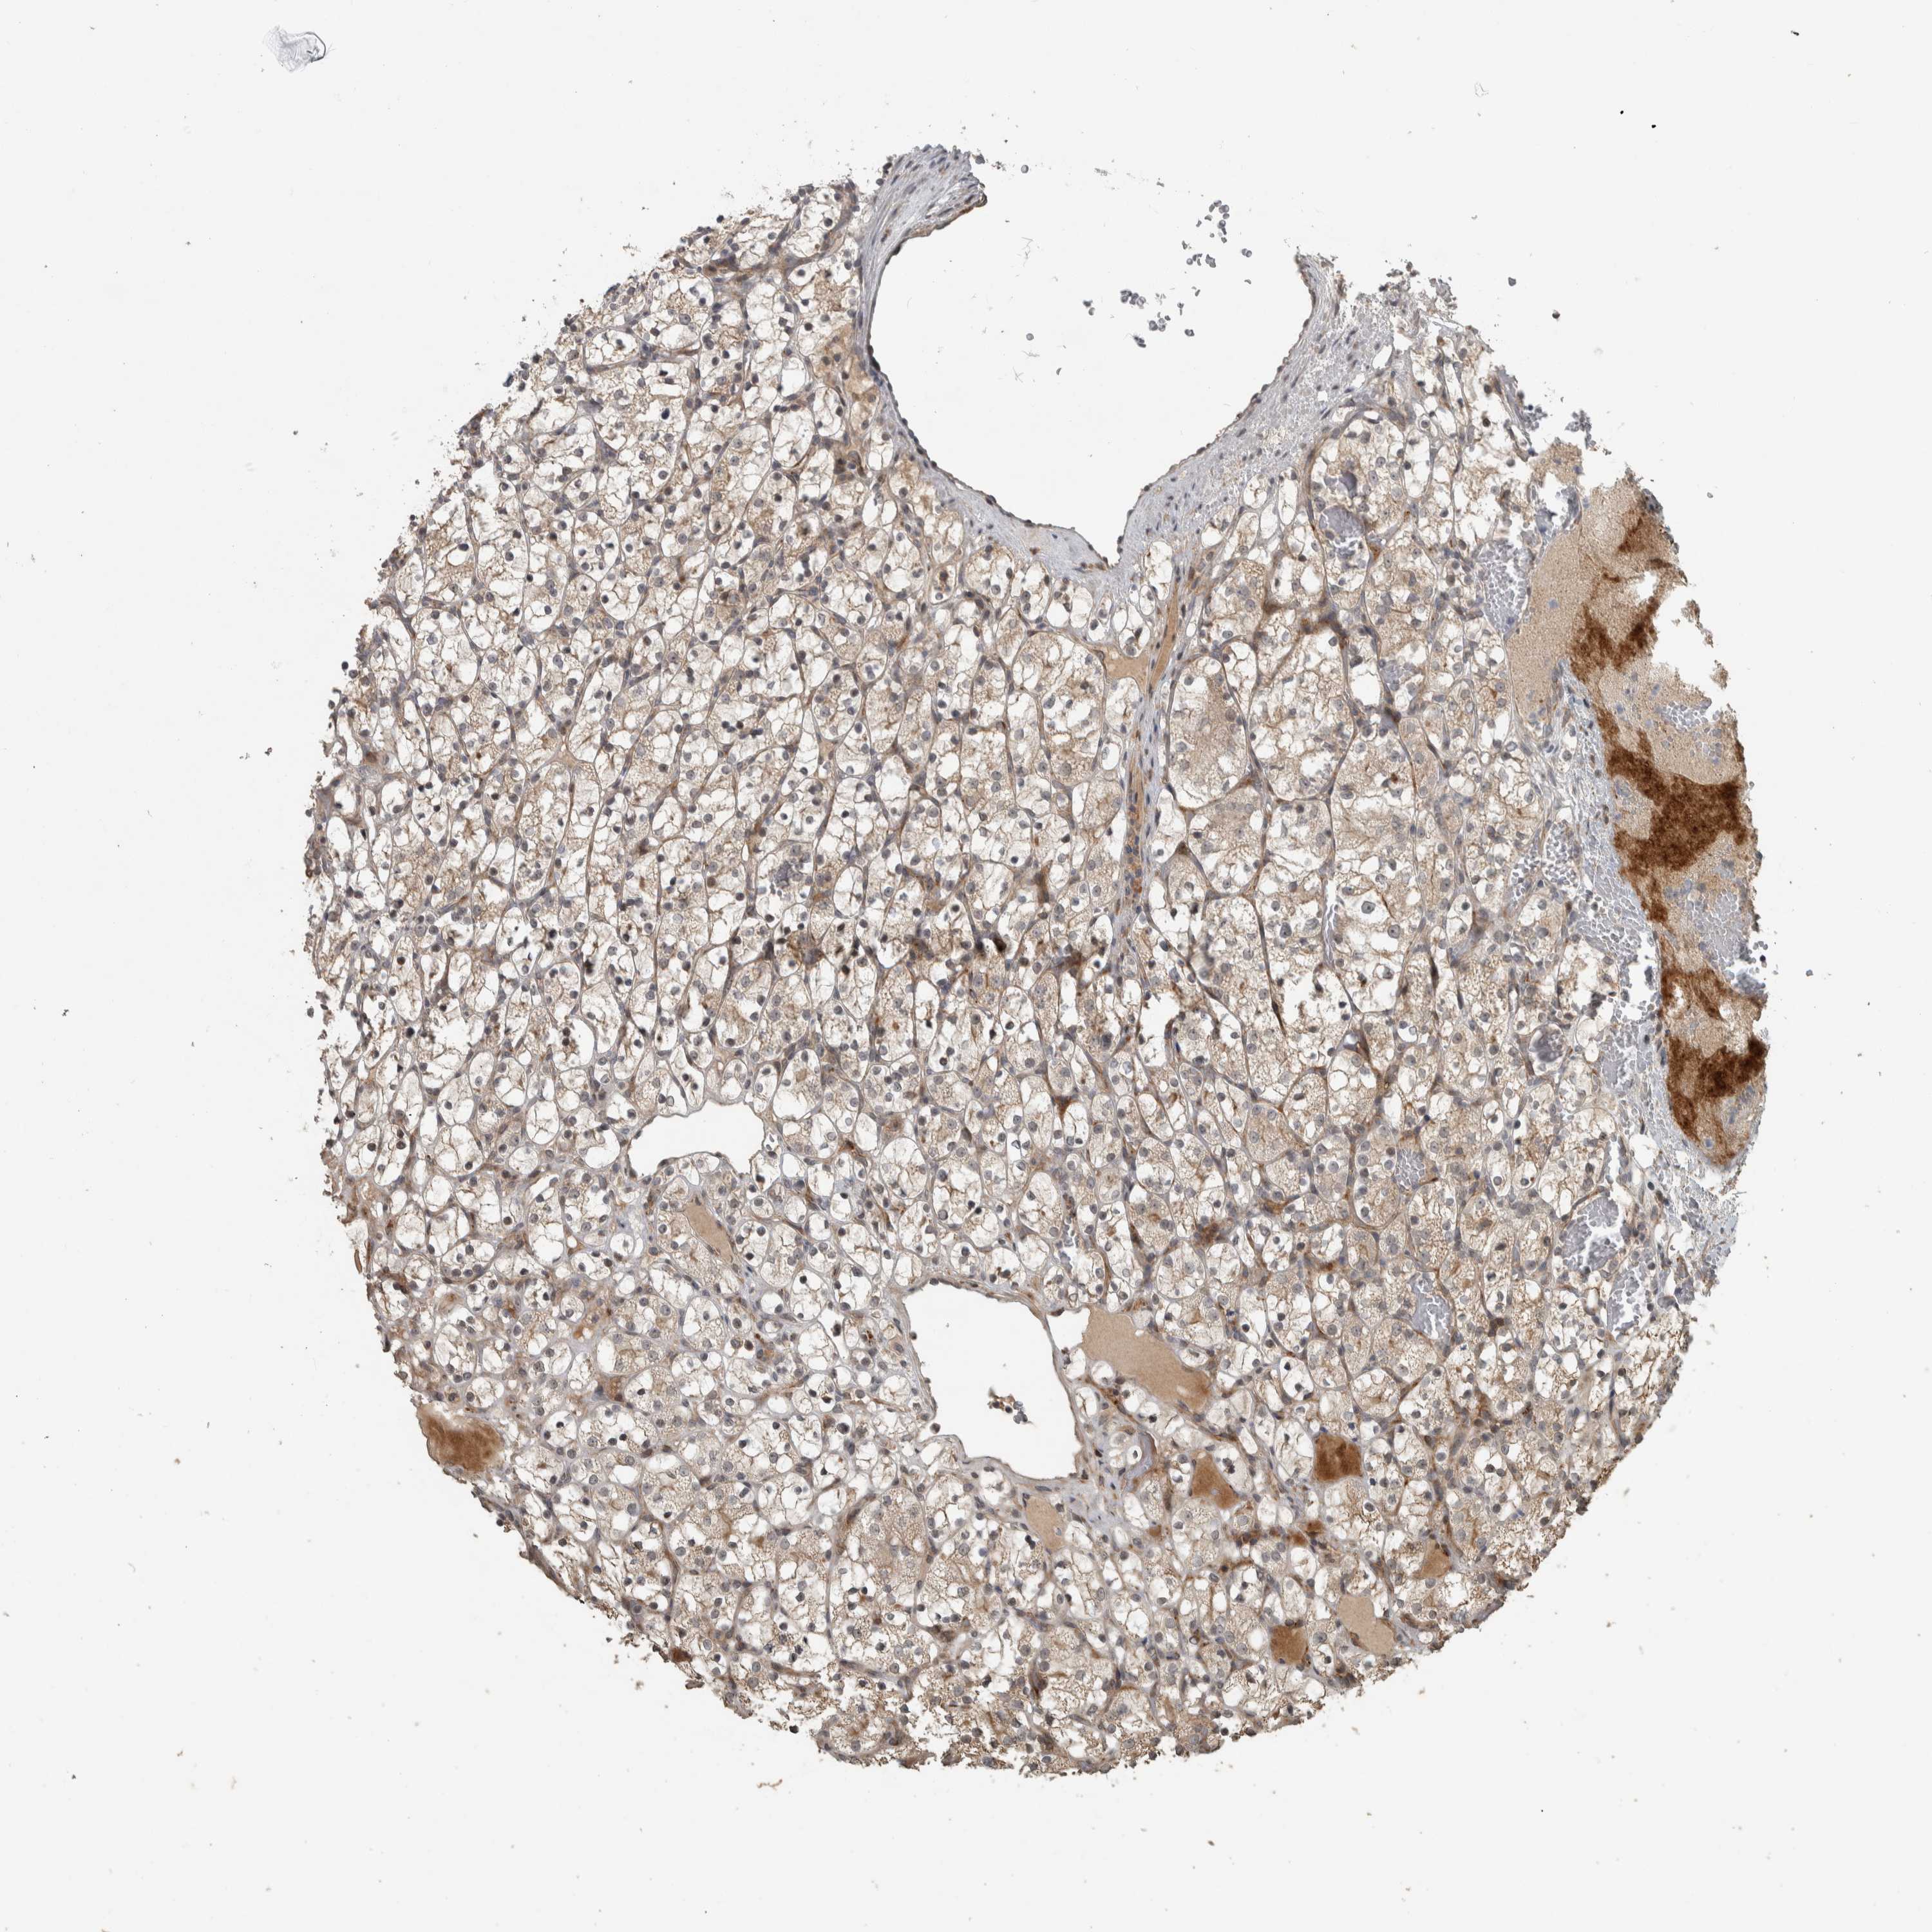

KIDNEY RENAL CLEAR CELL CARCINOMA (VALIDATION) - Interactive survival scatter ploti

The Survival Scatter plot shows the clinical status (i.e. dead or alive) for all individuals in the patient cohort, based on the same data that underlies the corresponding Kaplan-Meier plots. Patients that are alive at last time for follow-up are shown in blue and patients who have died during the study are shown in red.

The x-axis shows the expression levels (FPKM) of the investigated gene in the tumor tissue at the time of diagnosis. The y-axis shows the follow-up time after diagnosis (years). Both axes are complimented with kernel density curves demonstrating the data density over the axes. The top density plot shows the expression levels (FPKM) distribution among dead (red) and alive patients (blue). The right density plot shows the data density of the survived years of dead patients with high and low expression levels respectively, stratified using the cutoff indicated by the vertical dashed line through the Survival Scatter plot. This cutoff is automatically defined based on the FPKM cutoff that minimizes the p-score. The cutoff can be changed by dragging the vertical line or by entering a cutoff value in the square labeled "Current cut-off".

Under the Survival Scatter plot the p-score landscape (black curve; left axis) is shown together with dead median separation (red curve; right axis). Dead median separation is the difference in median mRNA expression between patients who have died with high and low expression, respectively. It is calculated as follows: median FPKM expression of dead patients with high expression - median FPKM expression of dead patients with low expression. This is intended to aid the user in visually exploring custom cutoffs and the associated p-scores and dead median separation.

Individual patient data is displayed and can be filtered by clicking on one or more of the category buttons on the top of the page. Categories describing expression level and patient information include: high, low, alive, dead, female, male and tumor stages. The scale of the x-axis can be toggled between linear and log-scale by clicking on the "x log" button. Mouse-over function shows TCGA ID, patient information and mRNA expression (FPKM) for each patient.

& Survival analysisi

Kaplan-Meier plots summarize results from analysis of correlation between mRNA expression level and patient survival. Patients were divided based on level of expression into one of the two groups "low" (under cut off) or "high" (over cut off). X-axis shows time for survival (years) and y-axis shows the probability of survival, where 1.0 corresponds to 100 percent.

ERAL1 is not prognostic in Kidney Renal Clear Cell Carcinoma (validation)

: 31.38

Average pTPM 30.4

Number of samples 100